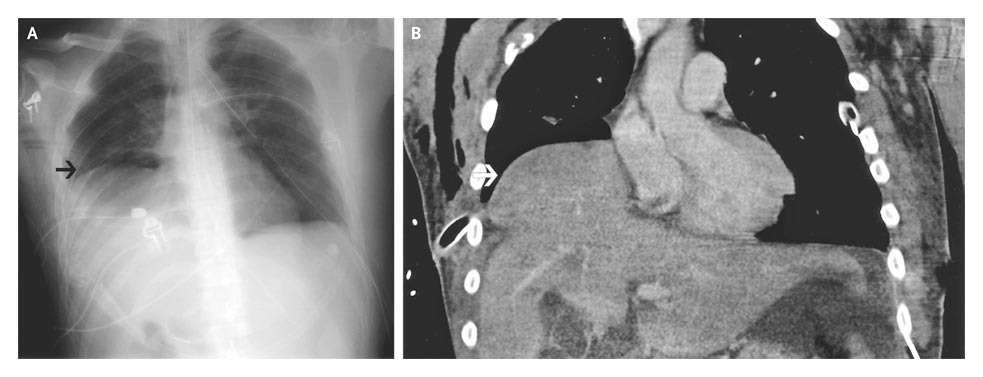

A computed tomographic scan confirmed the diaphragmatic rupture and showed that the dome of the liver had herniated into the right hemithorax (Panel B, arrow).